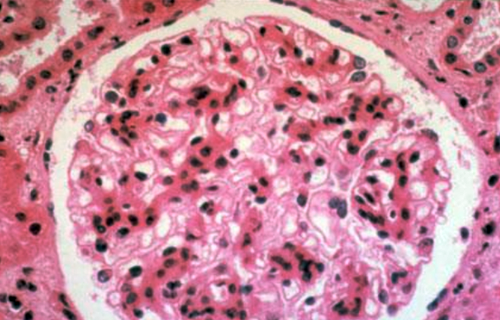

Гистология подагрической нефропатии: изучение тканей